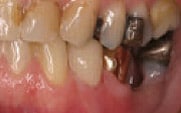

Figure 1

Initial situation:

Decay, fractured buccal cusp and unsupported lingual cusp on tooth

No. 20, buccal view.